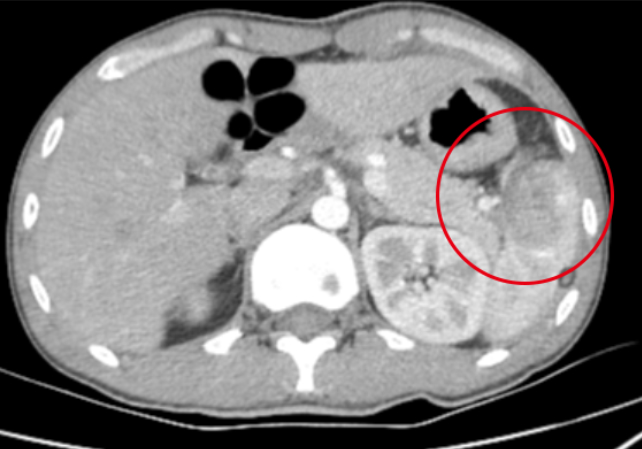

2025年5月31日清晨,23歲的李先生(化名)因騎電動(dòng)車不慎摔倒導(dǎo)致左側(cè)季肋區(qū)受傷、創(chuàng)傷性脾破裂,失血性休克。經(jīng)我院創(chuàng)傷中心團(tuán)隊(duì)緊急施救,成功實(shí)施脾修補(bǔ)手術(shù)?;颊呃钕壬诋?dāng)日清晨來(lái)院就診,主訴胸腹疼痛3小時(shí)。急診查體發(fā)現(xiàn)腹部壓痛、反跳痛伴肌緊張,腹部超聲提示"脾下極回聲雜亂、盆腔大量積血",凝血功能顯示纖維蛋白原降低至1.98g/L,D-二聚體升高至1.92mg/L,血常規(guī)白細(xì)胞計(jì)數(shù)顯著升高,急診團(tuán)隊(duì)迅速確診病情為"創(chuàng)傷性脾破裂合并失血性休克&2025-06-21